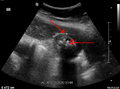

Mild gallbladder wall thickening of 3.5 mm in a person with acute cholecystitis as seen on ultrasound

Acute cholecysitis as seen on ultrasound. Closed arrow points to gall bladder wall thickening. Open arrow points to stones in the GB